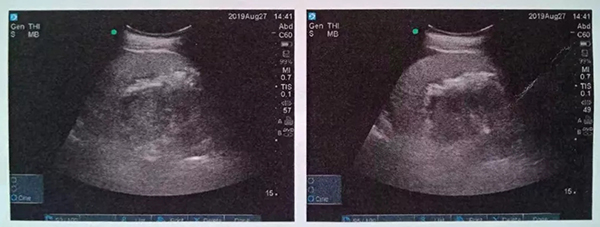

入院后經(jīng)細(xì)致檢查,診斷其為泌尿系結(jié)石,右腎積水,右輸尿管梗阻,30余年前曾在錢糧湖醫(yī)院行闌尾切除術(shù)及腸梗阻手術(shù)。由于患者右腎為重復(fù)腎合并結(jié)石,解剖結(jié)構(gòu)和病情極其復(fù)雜。泌尿外科周旭陽(yáng)主任組織科室專家進(jìn)行術(shù)前討論,決定在充分抗感染治療的基礎(chǔ)上行經(jīng)皮腎鏡鈥激光碎石術(shù)。

術(shù)中,泌尿外科郭駿博士精心設(shè)計(jì)手術(shù)通道,只在患者體表鉆出兩個(gè)0.5厘米的小洞,由于患者右側(cè)上位腎位置高,靠近肝臟和肺下葉,容易出現(xiàn)肝臟和肺的損傷,在B超的引導(dǎo)下精確穿刺腎結(jié)石的最高點(diǎn),逐級(jí)擴(kuò)張后建立皮腎通道。這時(shí)屢次“惹禍”的腎結(jié)石清楚的顯露在手術(shù)屏幕上,結(jié)石呈淺黃色,表面覆蓋淺褐色的膿苔,然后使用鈥激光將結(jié)石擊碎后取出。歷時(shí)一個(gè)半小時(shí),結(jié)石全部清除,手術(shù)結(jié)束。

術(shù)后CT,箭頭所指為腎結(jié)石被徹底清除

三日后,曾奶奶病情逐漸穩(wěn)定,各項(xiàng)感染指標(biāo)逐漸恢復(fù)正常,復(fù)查CT顯示腎結(jié)石已經(jīng)被完全清除,現(xiàn)已康復(fù)出院。就此,困擾曾奶奶多年,反復(fù)感染差點(diǎn)致命的腎結(jié)石頑疾被徹底治愈。曾奶奶全家人對(duì)于愛康醫(yī)院泌尿外科專家高超的碎石取石手術(shù)技藝更是贊許有加,對(duì)泌尿外科團(tuán)隊(duì)的工作給予衷心感謝和高度評(píng)價(jià)。